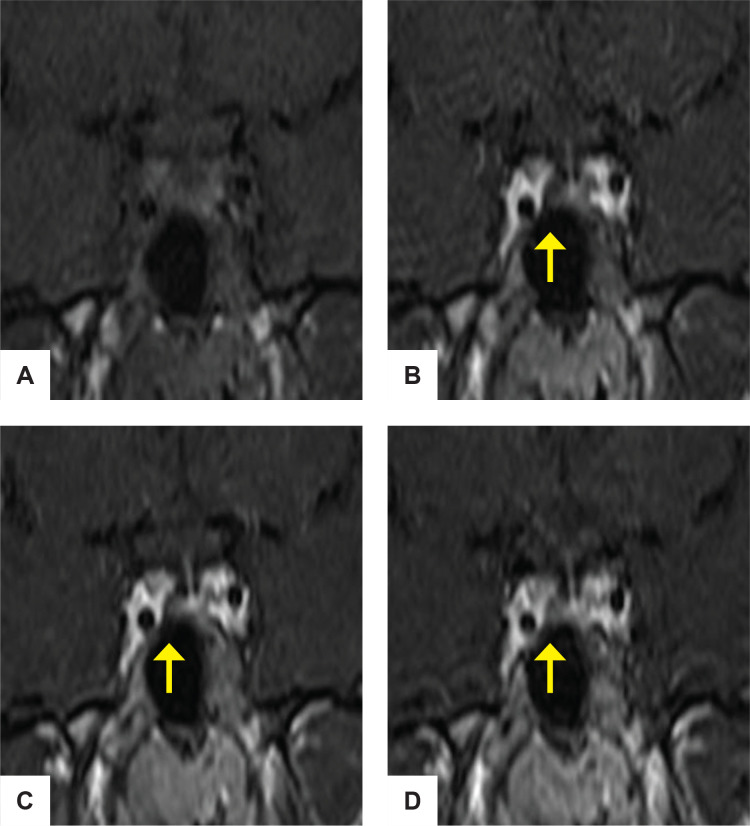

处理一个同时有垂体高分泌和低分泌表现的病人可能是令人困惑的。我们报告一个14岁的女性谁提出体重增加,多尿和烦渴。生化结果与库欣病合并中枢性尿崩症一致。垂体磁共振成像显示右侧腺瘤伴茎部增厚。两种腺瘤的免疫组化染色均为促肾上腺皮质激素、促甲状腺激素、生长激素和促黄体生成素阳性。术后,患者出现垂体功能减退并持续性尿崩症。双腺瘤的共存会给诊断和治疗带来挑战,也是手术失败的常见原因。术中评估是识别双重或多重垂体腺瘤的重要患者呈现多种分泌表现。

Managing a patient with both pituitary hypersecretory and hyposecretory manifestations may be perplexing. We report a 14-year-old female who presented with weight gain, polyuria and polydipsia. Biochemical results were consistent with Cushing disease with central diabetes insipidus. Pituitary magnetic resonance imaging showed a right adenoma with stalk thickening. The immunohistochemistry staining of both adenomas was positive for adrenocorticotropic hormone, thyroid stimulating hormone, growth hormone and luteinizing hormone. Postoperatively, the patient developed panhypopituitarism with persistent diabetes insipidus. The coexistence of double adenomas can pose diagnostic and management challenges and is a common cause of surgical failure. Intraoperative evaluation is important in the identification of double or multiple pituitary adenomas in a patient presenting with multiple secretory manifestations.